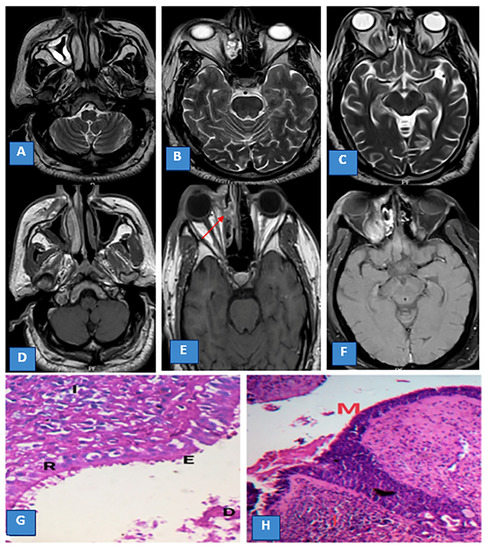

3.2. Sinonasal Involvement

3.3. MRI Findings and Signal Characteristics

3.4. Extrasinus Extension

3.5. Histopathological Findings